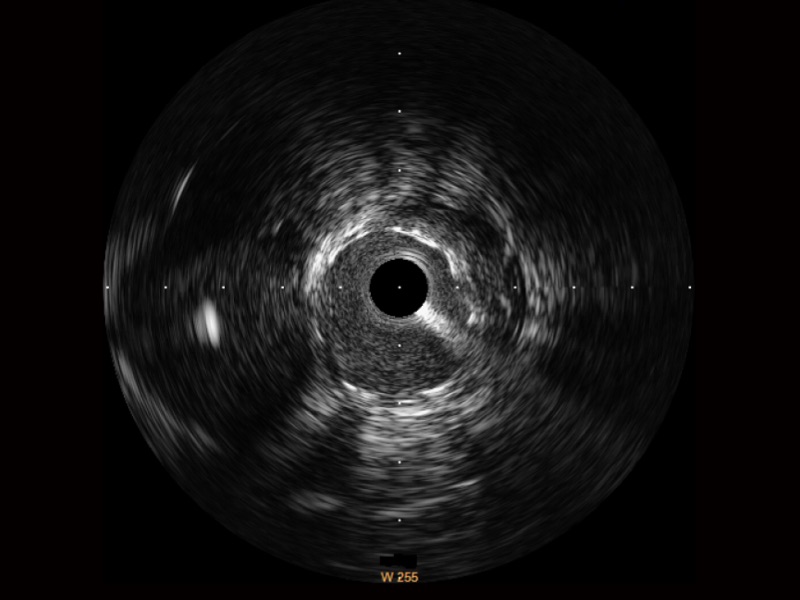

诸侯快讯官网宽频IVUS图像

传统IVUS图像

对比传统IVUS导管成像,诸侯快讯官网宽频IVUS图像的近场支架梁显影更细腻,远场中膜外血管仍清晰可辨,兼顾远中近,兼顾分辨力与穿透深度